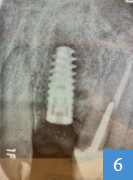

implant dentaire en place

6 : implant dentaire en place

(merci au Dr L. Tournier pour cette radiographie)